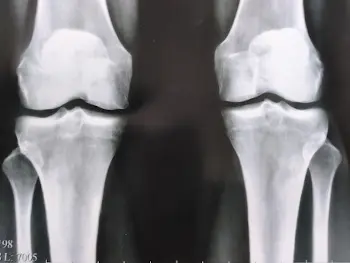

এই ছবিগুলো দেখো। সঠিক ছবিতে, জয়েন্টের জায়গা নেই, হাড়গুলো একে অপরের সাথে ঘষছে, যার ফলে তীব্র ব্যথা হচ্ছে। আর এই প্রক্রিয়া বন্ধ করা খুব কঠিন! কয়েক বছরের মধ্যে, ব্যক্তিটি অক্ষম হয়ে যাবে এবং নিজের যত্ন নিতে পারবে না।

এই সবই তরুণাস্থি টিস্যুকে নরম করে, জীর্ণ করে এবং পাতলা করে। প্রতিটি নতুন নড়াচড়ার সাথে, তরুণাস্থি জীর্ণ হয়ে যায় এবং বিকৃত হয়ে যায়, হাড়গুলি একে অপরের সাথে ঘষতে শুরু করে, যার ফলে অসহনীয় ব্যথা হয়।